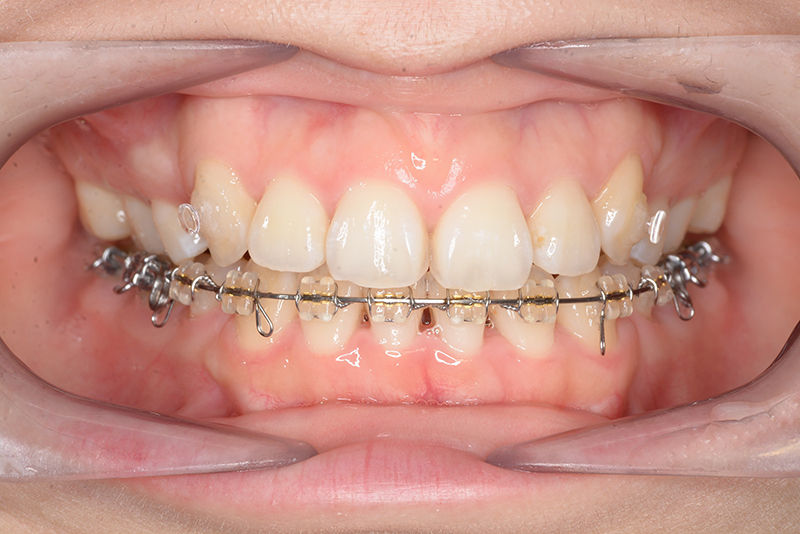

| 口腔内所見 | over jet 4.5mm、over bite 4.0mm、大臼歯関係 I級で上下顎前歯部に叢生が認められた。 |

| 批評・予后 | 叢生が大きかった影響もあり、治療期間は20ヶ月と比較的短い期間が終了できた。治療後においては口元の改善、咬合の緊密化は達成できたように思う。 |